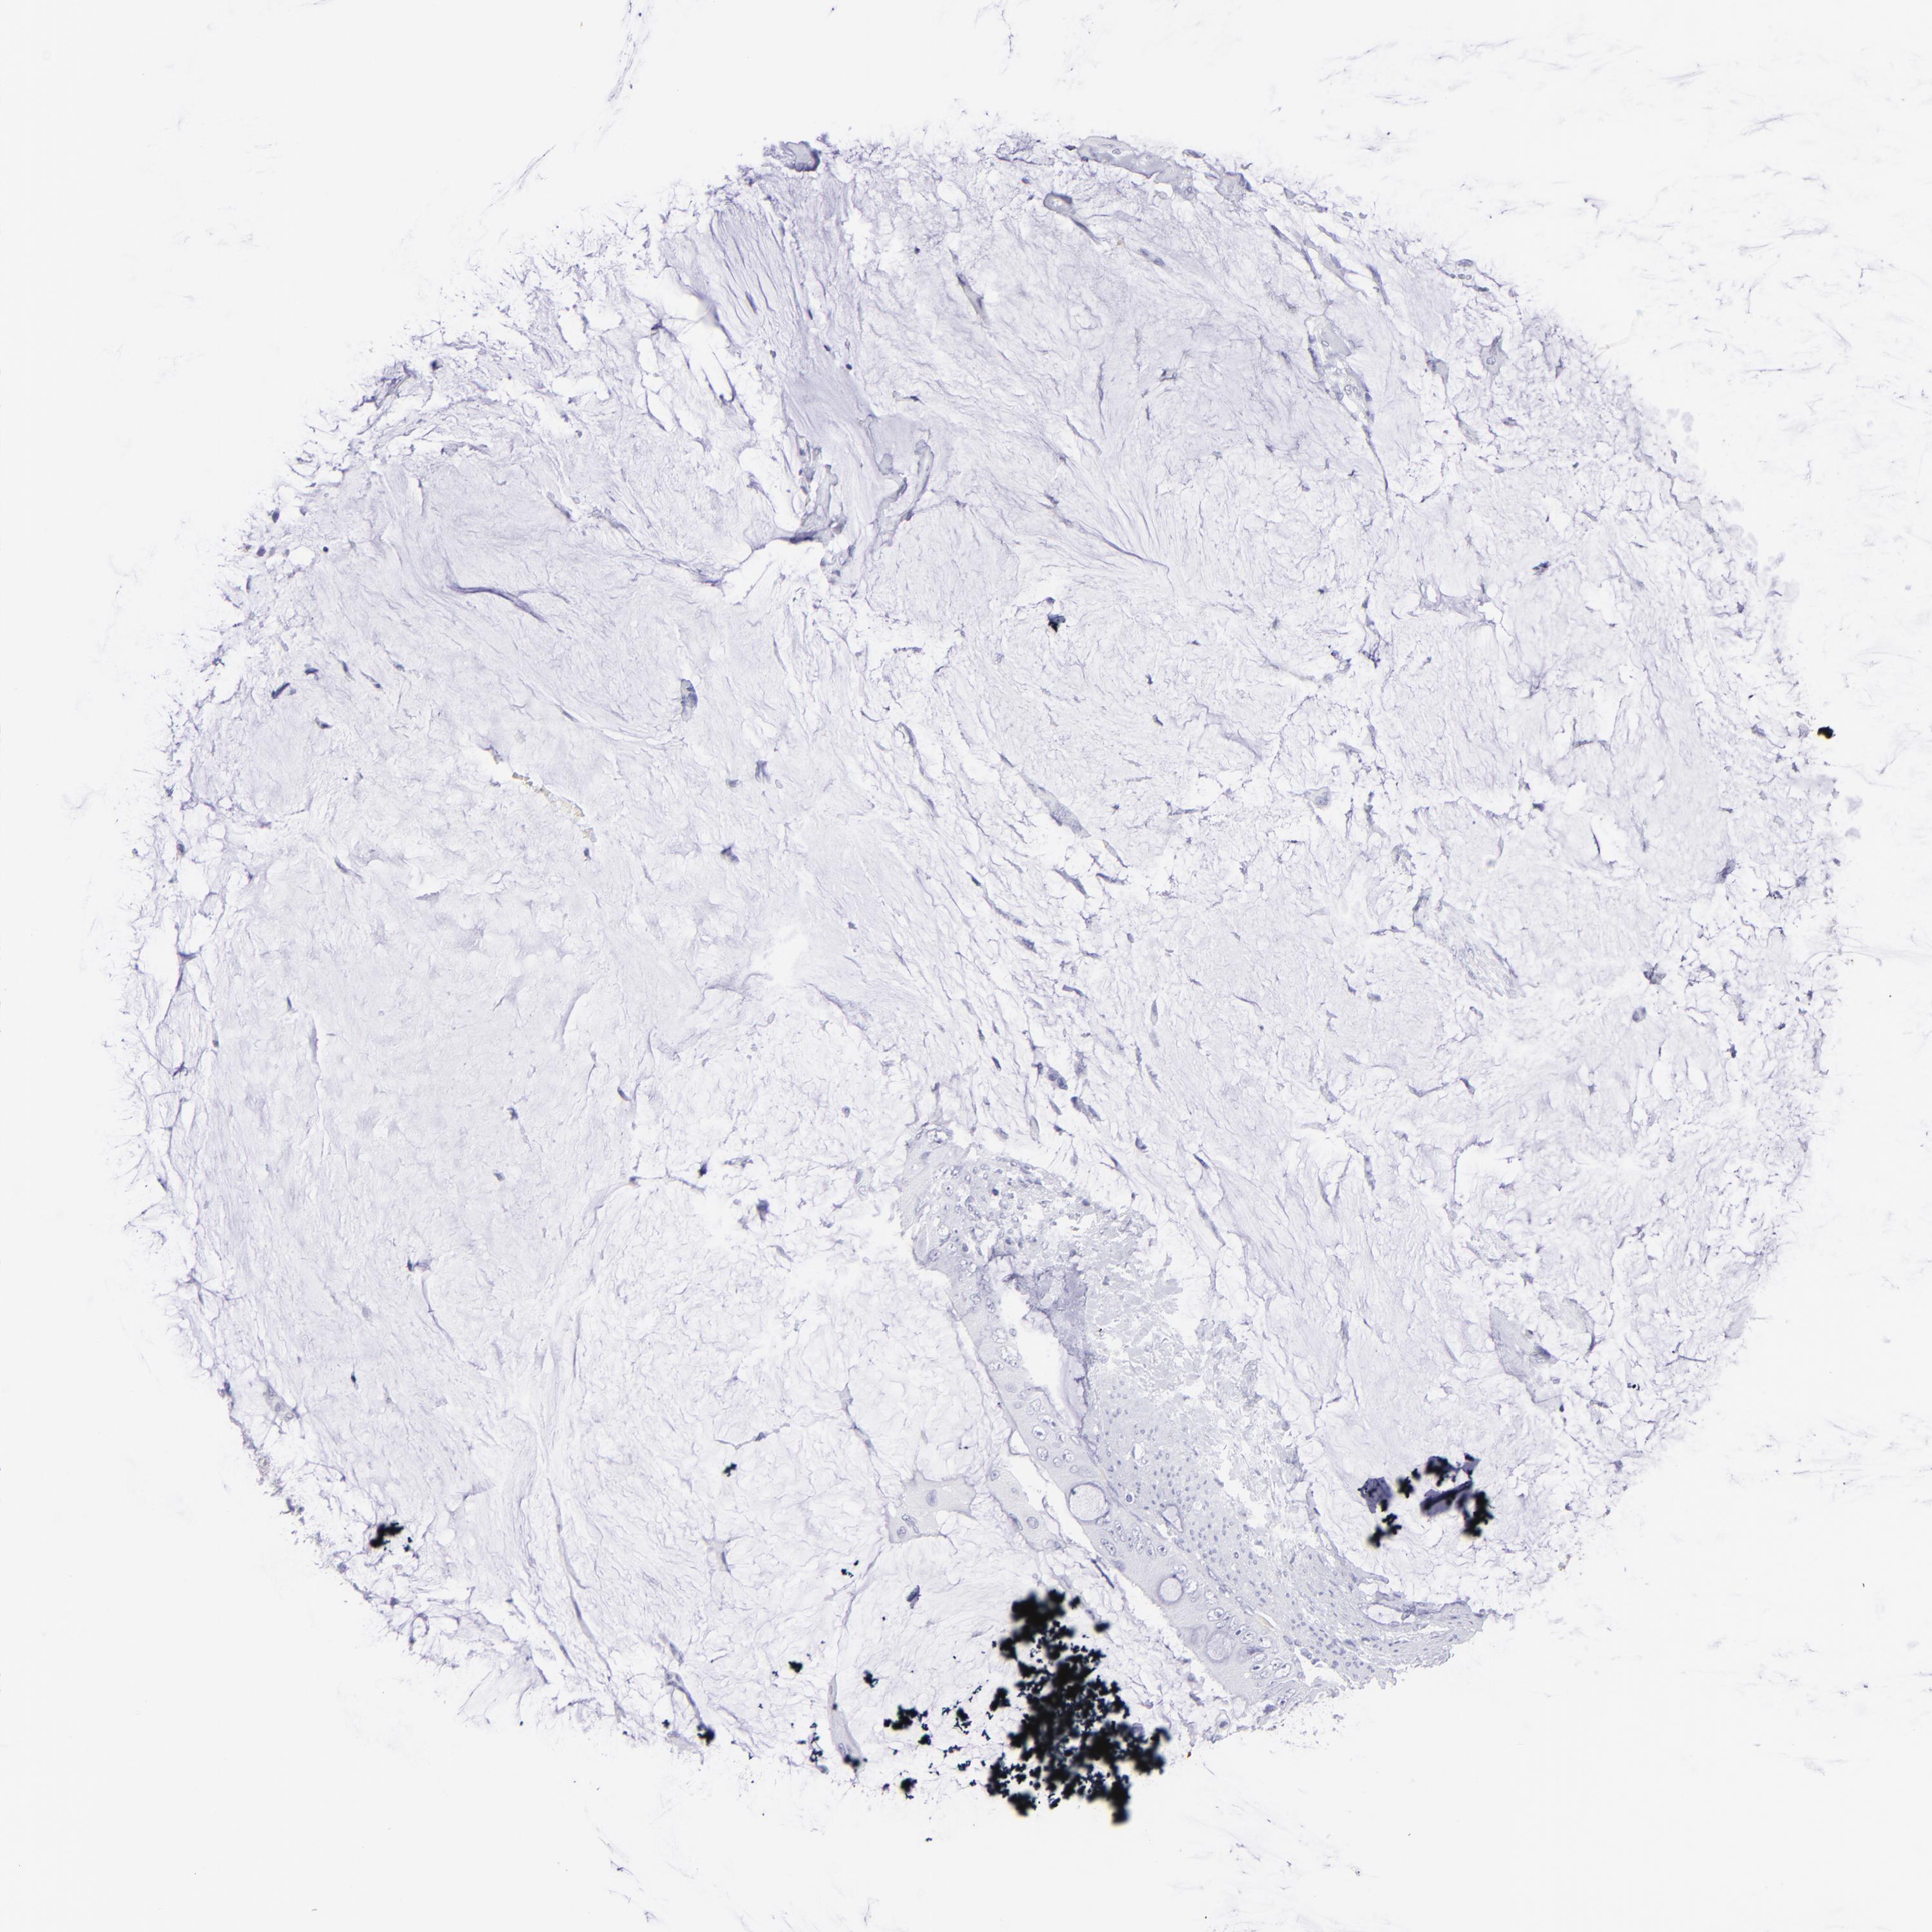

Colorectal cancer

Rectum adenocarcinoma